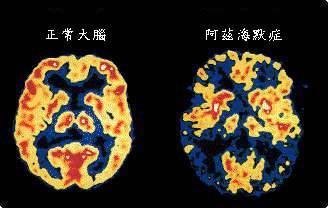

▲老年痴呆症,也叫“阿尔茨海默症”。与正常人的大脑相比,老年痴呆症患者大脑出现了萎缩